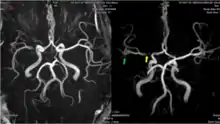

The leptomeningeal collateral circulation (also known as leptomeningeal anastomoses or pial collaterals) is a network of small blood vessels in the brain that connects branches of the middle, anterior and posterior cerebral arteries (MCA, ACA, and PCA),[1] with variation in its precise anatomy between individuals.[2] During a stroke, leptomeningeal collateral vessels allow limited blood flow when other, larger blood vessels provide inadequate blood supply to a part of the brain.[3]

MRI and CT brain imaging is used to determine the severity of a stroke, and help guide treatment. Fluid attenuated inversion recovery (FLAIR) vascular hyperintensity (FVH) is a radiographic marker seen on brain imaging in acute ischaemic stroke. FVH can be used as a proxy for slow leptomeningeal collateral blood flow, and may help reveal which areas of brain tissue are potentially salvageable.[12]